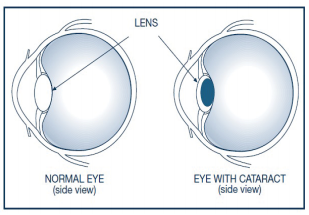

The most common cause is growing older. Other common causes include:

It treats dry eyes by improving the function of the meibomian (oil) glands of the eyelids. Meibomian glands that are not functioning properly can eventually lead to gland dropout (loss) or atrophy, which leads to long-term and severe dry eye symptoms. When meibomian glands don’t secrete enough oil onto the eye, tears evaporate too quickly, leading to a cycle of inflammation.

It treats dry eyes by improving the function of the meibomian (oil) glands of the eyelids. Meibomian glands that are not functioning properly can eventually lead to gland dropout (loss) or atrophy, which leads to long-term and severe dry eye symptoms. When meibomian glands don’t secrete enough oil onto the eye, tears evaporate too quickly, leading to a cycle of inflammation.

This leads to dry eye symptoms such as burning sensation, stinging, irritation, tearing, and redness. By restoring gland function, IRPL can make sure your eyes have the proper hydration.